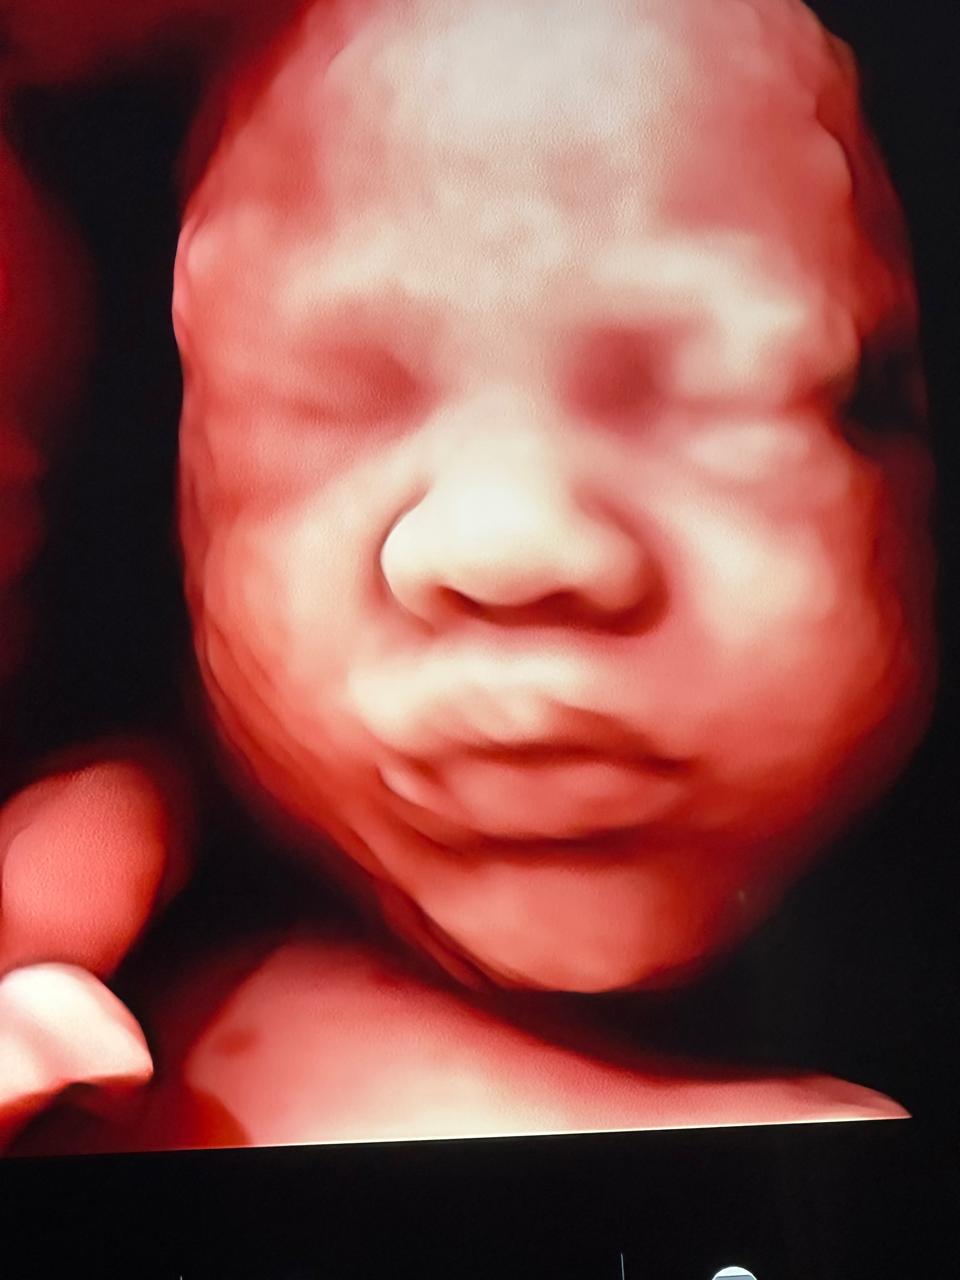

Entre los estudios ecográficos que ofrece se encuentran:

• Ecografía Morfológica Doppler (Semanas 16-26): Un estudio detallado de cada parte del cuerpo fetal (cerebro, corazón, columna, órganos y extremidades) para descartar anomalías estructurales.

• Ecografía de Crecimiento Doppler (Semanas 28-36): Evalúa el crecimiento fetal y la función placentaria para asegurar que el peso del bebé sea el adecuado para su edad gestacional.